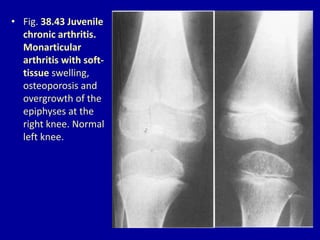

• Fig. 38.43 Juvenile

chronic arthritis.

Monarticular

arthritis with soft-

tissue swelling,

osteoporosis and

overgrowth of the

epiphyses at the

right knee. Normal

left knee.

• Fig. 38.43Juvenile chronic arthritis. Monarticular arthritis with soft- tissue swelling, osteoporosis and overgrowth of the epiphyses at the right knee. Normal left knee.